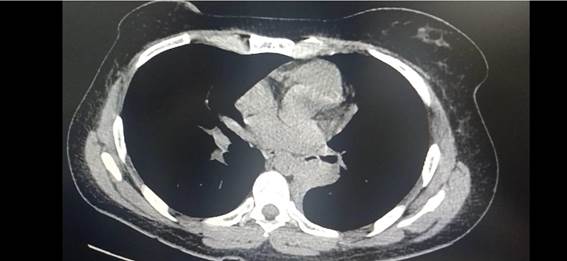

TC cuello, tórax, abdomen y pelvis: Atelectasia del lóbulo inferior izquierdo con obstrucción del bronquio lobar inferior próximo a su origen. Sin adenopatías.Figura 3.